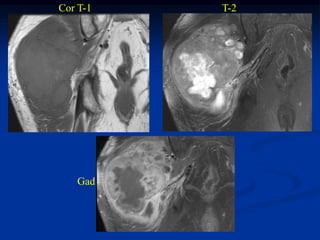

Case #261

62 year female

MFH anterior thigh

AP x-ray

Sagittal proton

density MRI

Sagittal T-2 MRI

Axial proton density MRI

Axial T-2 MRI